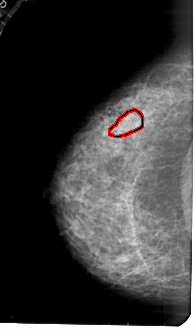

A_1777_1.LEFT_MLO

LEFT_MLO LINES 5491 PIXELS_PER_LINE 3106 BITS_PER_PIXEL 12 RESOLUTION 43.5 OVERLAY

FILE: A_1777_1.LEFT_MLO.OVERLAY

TOTAL_ABNORMALITIES 1

ABNORMALITY 1

LESION_TYPE MASS SHAPE ARCHITECTURAL_DISTORTION MARGINS ILL_DEFINED

ASSESSMENT 4

SUBTLETY 2

PATHOLOGY BENIGN

TOTAL_OUTLINES 1

BOUNDARY